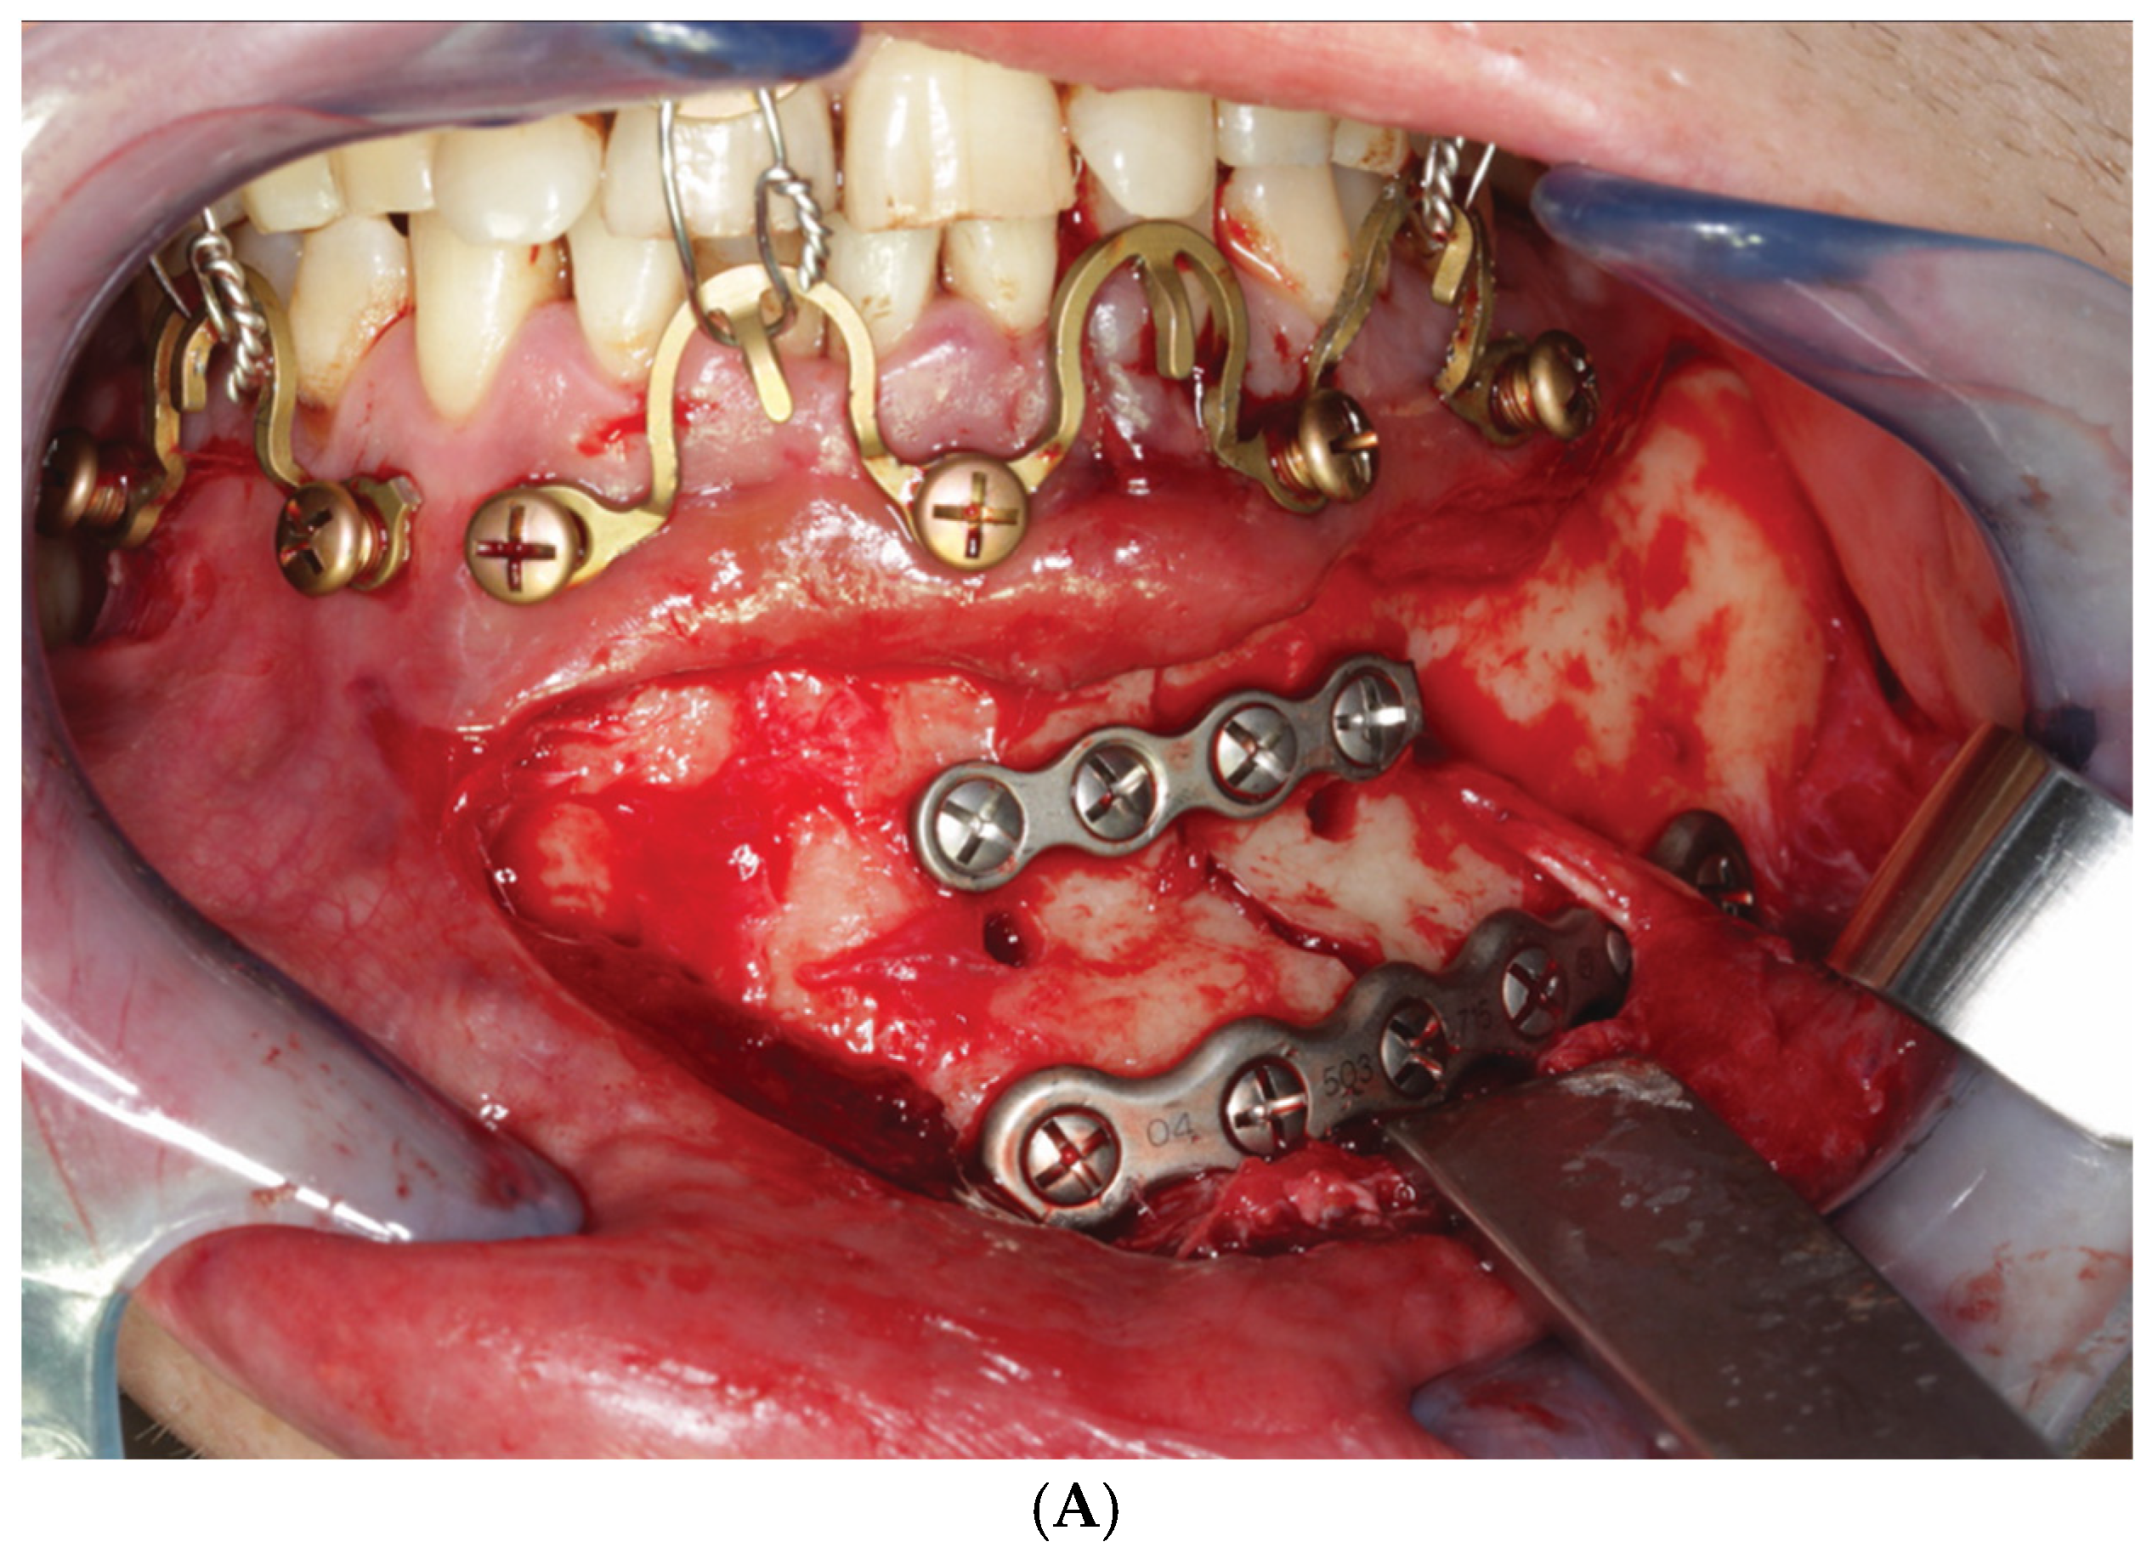

3.3. ‘In-Situ-Bending’ for Fracture Reduction